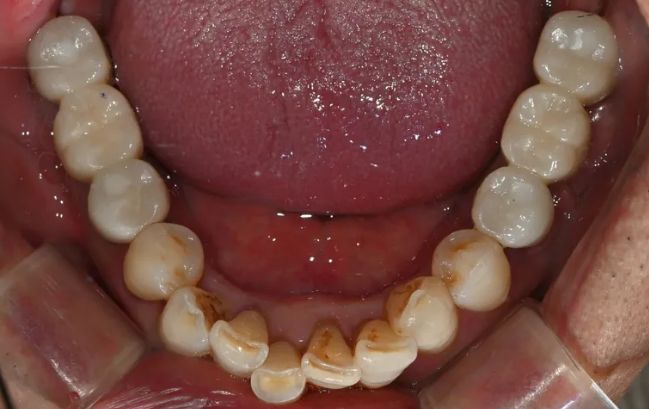

2021-09-06

2022-03-0560대 남성, 수면 전체 임플란트 13개 식립